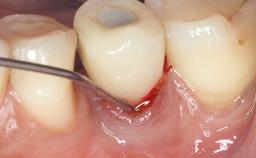

Treatment of Peri-Implantitis at a Zirconia Implant

Due to their promising clinical performance, zirconia implants have recently become popular alternatives to titanium implants, particularly for areas with high esthetic demands (Holländer and coworkers 2016; Roehling and coworkers 2016; Lorenz and coworkers 2019). However, regardless of the reported high survival and success rates, zirconia implants were affected by peri-implant diseases over the short observation period, suggesting the importance of treating peri-implant diseases at zirconia implants (Becker and coworkers 2017). In their case, Frank Schwarz and Ausra Ramanauskaite present 3-year results following mechanical debridement alongside Er:YAG laser monotherapy.